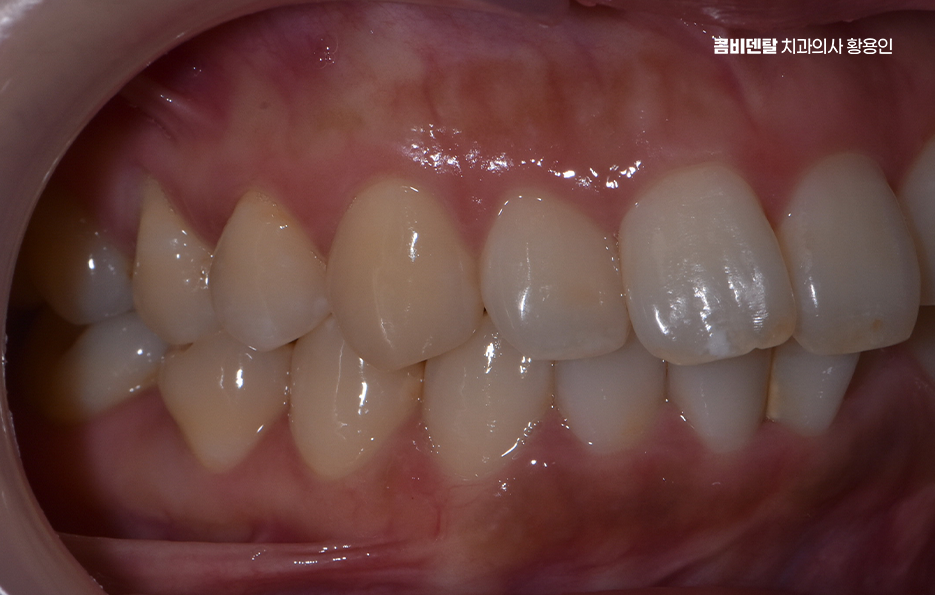

어린 시절엔 이가 조금 삐뚤한 걸 신경 쓰지 않고 자랐고 주변 어른들도 “크면 괜찮아진다”, “어릴 땐 다 그런 거야” 하며 넘겼지만, 성인이 되고 나서 거울을 볼 때마다 앞니 쪽만 유독 튀어나와 있고 비뚤게 배열된 걸 자각하게 되면서 말을 할 때도 윗니가 보이지 않도록 입 모양을 억지로 조절하는 자신을 발견하고는 이건 단순히 외모의 문제가 아니라는 생각이 들기 시작했어요. 앞니 네 개 정도만 유독 튀어나와 있고, 송곳니와 그 뒤 어금니는 정렬이 비교적 괜찮아서 전체 교정은 너무 과한 선택 같기도 했어요 또 주변에서 듣기로는 부분교정이라는 방법도 있다기에 관심을 갖게 되었어요, 그런데 막상 치과에 상담을 가보려고 하니 고민이 많아졌어요, 과연 부분교정만으로도 신경 쓰는 앞니 배열이 정말 개선될 수 있을까, 전체 치아의 균형이나 교합에는 문제가 생기지 않을까, 혹은 나중에 후회하게 되는 건 아닐까 하는 여러 걱정이 겹쳤어요

이처럼 유독 앞니 쪽 위주로 치아교정을 고민하는 분들에게는 부분교정이라는 치료 방법이 있다는 것 만으로도 치아교정을 좀더 적극적으로 결심하게 되는 계기가 되곤 하지만 막상 부분교정이 가능한 케이스는 많지 않다보니 막연하게 부분교정에 대해 간단하니 좋겠다 라고 느끼거나 앞니만이라도 가지런해지길 바라는 마음에 접근하는 것은 주의하실 필요가 있는데요

앞니 부분 교정이라는 건 말 그대로 전체 치아를 전반적으로 움직이는 게 아니라, 웃을 때 보이는 앞니 위주로 배열이나 틀어짐, 벌어짐 등을 정리하는 방식으로 앞니 부분 교정은 치료 시간과 비용, 교정 장치에 대한 부담을 줄일 수 있어서 치료가 가능한 케이스에 해당된다면 앞니를 전체교정에 비해 빠르게 개선할 수 있어요

앞니 부분 교정은 단순히 환자분이 원한다고 선택 가능한 것은 아니며 앞니만 따로 움직일 수 있을 만큼 주변 치아나 교합 상태가 안정적인 경우여야만 적용이 가능한 거예요.

그래서 단순히 앞니 사이가 벌어졌거나, 살짝 돌아가 있거나, 비대칭으로 삐뚤어진 경우처럼 부분적인 배열 문제일 때, 즉 전체적인 교합이나 턱의 위치에는 큰 문제가 없고 미세한 심미적인 조정이 필요한 경우에만 앞니 부분 교정이 효과적으로 작용한다고 볼 수 있어요